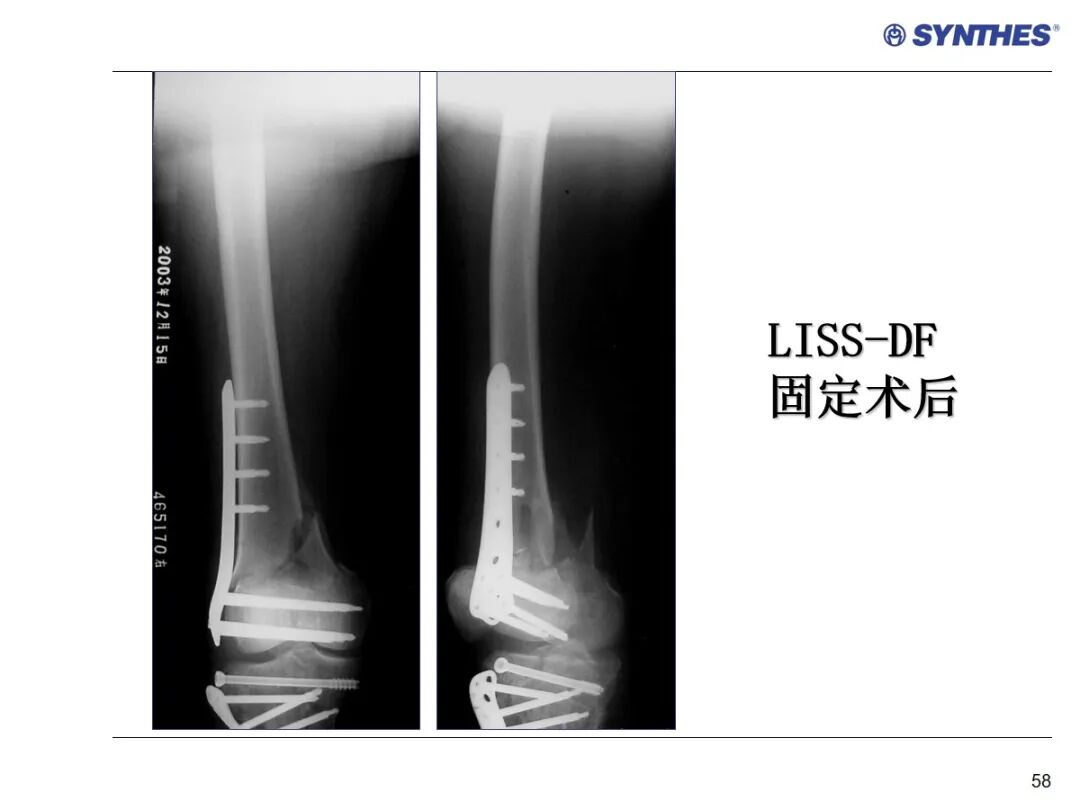

LISS微创固定系统应用技巧,原来如此简单!